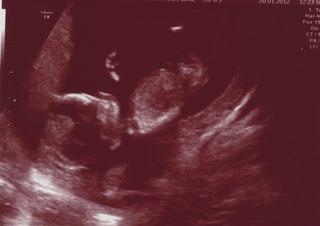

Ahojky holky, tak screening dopadl parádně, máme zdravé miminko. Hodnoty jsou super, nevím, jestli je tady mám psát, když tak to dopíšu. 🙂 měříme už 7,2cm. a doktor říkal, že to vypadá na 14. týden, a né na 13. jak původně říkali, ale zatím mi nic neměnil, protože to nebyl přímo můj gynekolog, na kontrolu jdu až 14.2. tak mi můj doktor řekne co a jak, jestli mi to nějak přehodí ten termín porodu, nebo co. takže uvidíme. 😉 Manžel byl úplně na měkko a já taky. bylo to úžasné. přikládám fotečku. 🙂 🙂

a co vy děvčátka nějaké novinky? 🙂

@trolleey Krááásný, moc gratuluju moc, člověk si hnedka oddychne co ? 🙂 písni hodnoty, jsem zvědavá 🙂 No vídíš to, jak jste krásně velicí 🙂 my jsme měli v 13.týdnu 5,7cm, tak si myslim, že jsi víc 🙂 moc gratuluju 🙂 Jinak mě je dneska nějak divně, pořád mě popichuje v břiše, ale to možná přisuzuju obědu (fazolky 😀 ) a začali mě bolet záda, strašně moc, tak doufám, že se z toho vyspim :( :(